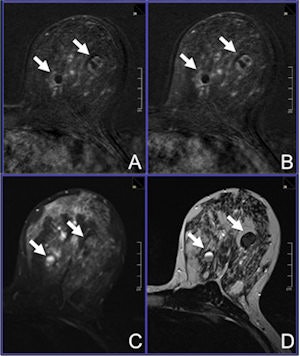

A 42-year-old woman was referred to MRI due to dense breast tissue and multiple cystic lesions, several of them showing inhomogeneous echogeneity and dorsal acoustic shadowing, classified as BI-RADS 0. A: Early contrast-enhanced T1-weighted subtraction. B: Delayed contrast-enhanced T1-subtraction. C: Short tau inversion-recovery image. D: T2-weighted, turbo spin-echo image reveals the lesions to be proteinaceous cysts (arrows). Image courtesy of Dr. Claudio Spick.